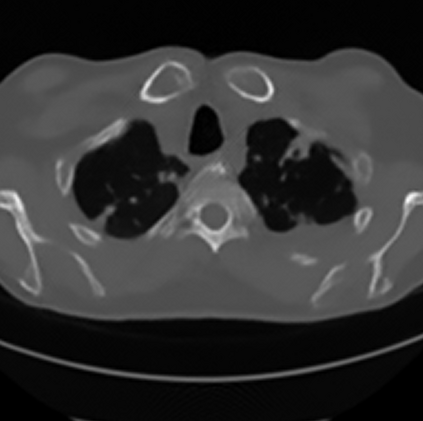

Sparse-view computed tomography (CT) -- using a small number of projections for tomographic reconstruction -- enables much lower radiation dose to patients and accelerated data acquisition. The reconstructed images, however, suffer from strong artifacts, greatly limiting their diagnostic value. Current trends for sparse-view CT turn to the raw data for better information recovery. The resultant dual-domain methods, nonetheless, suffer from secondary artifacts, especially in ultra-sparse view scenarios, and their generalization to other scanners/protocols is greatly limited. A crucial question arises: have the image post-processing methods reached the limit? Our answer is not yet. In this paper, we stick to image post-processing methods due to great flexibility and propose global representation (GloRe) distillation framework for sparse-view CT, termed GloReDi. First, we propose to learn GloRe with Fourier convolution, so each element in GloRe has an image-wide receptive field. Second, unlike methods that only use the full-view images for supervision, we propose to distill GloRe from intermediate-view reconstructed images that are readily available but not explored in previous literature. The success of GloRe distillation is attributed to two key components: representation directional distillation to align the GloRe directions, and band-pass-specific contrastive distillation to gain clinically important details. Extensive experiments demonstrate the superiority of the proposed GloReDi over the state-of-the-art methods, including dual-domain ones. The source code is available at https://github.com/longzilicart/GloReDi.